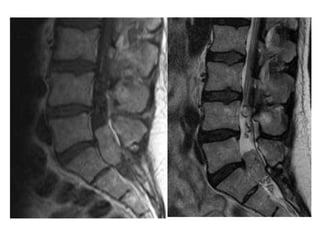

P. E.  65 years old He presented with a long history of immobility and progressive deterioration in his level of function.  Unable to feed himself, turn in bed or do any activities of daily living.  He had been bed bound for about a month. He had clear signs of cervical myelopathy

Lumbar MRI (sagittal view)